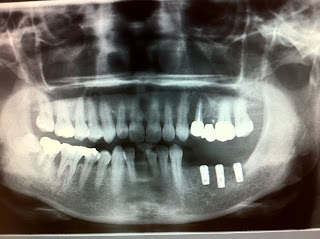

今週のオペは右下6・7・8番の部位にアストラインプラント直径4.0㎜ 長さ9を2

本とITIインプラントWN 長さ10㎜を1本の合計3本埋入しました。

右下7は去年の5月に歯周病で抜歯しており、かなり骨が無くなっていたので採血をしてCGFを利用して自家骨と人工骨を混ぜてGBRを右下7・8番の部位に実施しました。

今週のオペは右下6・7欠損で、ITIインプラントWN 長さ10㎜を2本埋入しました。

今週のオペは左下4~7番の部位にアストラインプラント直径4.0㎜ 長さ11・9㎜を合計3本埋入しました。

左下4は今年の1月に抜歯したので骨が十分で出来ておらず、左下7も2~3年前に抜歯したようですが中が空洞のように骨がなくいずれもGBRしました。